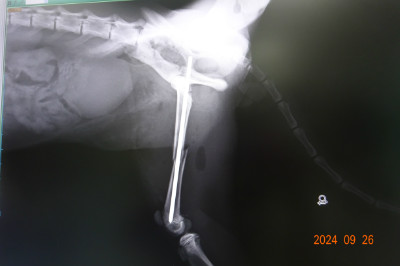

写真は昨日手術した大腿骨折の手術前のレントゲン写真です。

手術後の写真は、詳細参照。